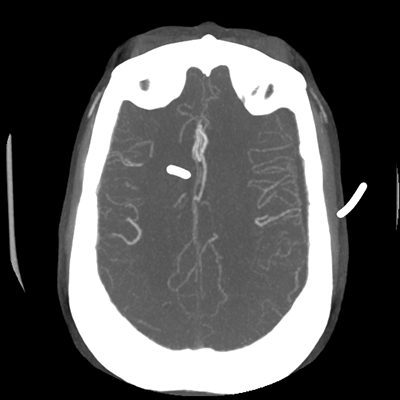

The patient goes down to CT. The following images are obtained. The subdural fluid collection is stable, as is the ventricular caliber.

CTA head (MIP)

Starting with the non-contrast head CT, we can appreciate that there's actually not much residual subarachnoid blood at all; it's essentially all resorbed already (and cleared through the EVD). The ventricular caliber is stable. With the CTA head (for convenience's sake, the MIPs were shown), it's subtle, but we can see that the PCAs on each side are not as smooth and regular. The right MCA, starting at the bifurcation, also becomes narrower. This is [radiographic] vasospasm. Now, looking at the CT perfusion-- specifically, the Tmax (MTT) map that were selected-- there's clearly some abnormality within the bilateral cerebellar hemispheres and occipital lobes. Not a lot, but it's there. Delving further into this map, we can appreciate that the areas of abnormality are mainly green, signifying that these areas have Tmax > 6 seconds. This is the threshold that is specific, not sensitive, for vasospasm.

Putting this all together, we have thus identified radiographic vasospasm with the vessel imaging, with perfusion abnormalities that are concordant with it. Does the area of vasospasm and hypoperfusion correlate with the patient's clinical exam?

Yes! It does. The patient had a decline in level of consciousness with diffuse loss of motor function. This does correlate to the basilar territory. (Alternatively, bilateral MCA vasospasm could also be responsible, reminding us that a decline in consciousness could technically be focal/multifocal.) Thus, we can say that this patient does have clinical vasospasm. Whether this will develop into irreversible DCI remains to be seen; at least, the non-contrast head CT and the other portions of the CT perfusion (not shown) currently don't [yet] suggest infarction.